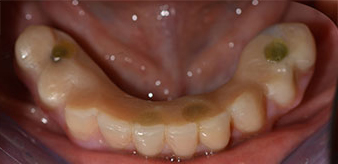

Un CT Scan à faisceaux coniques tridimensionnel (CBCT, Planmeca) a été réalisé au préalable afin de réduire les risques. Il a révélé une qualité et une quantité d'os disponible suffisante pour l'intervention chirurgicale et la restauration immédiate par la méthode All-on-four. En suivant le protocole de ce concept, les implants sont insérés au niveau de 35, 32, 42 et 45 en inclinant les implants distaux jusqu'à 45°, le profil d'émergence se déplace ainsi vers l'arrière et produit un polygone de stabilisation plus large (Fig. 3).

Méthode Fast & Fixed

Fig. 3